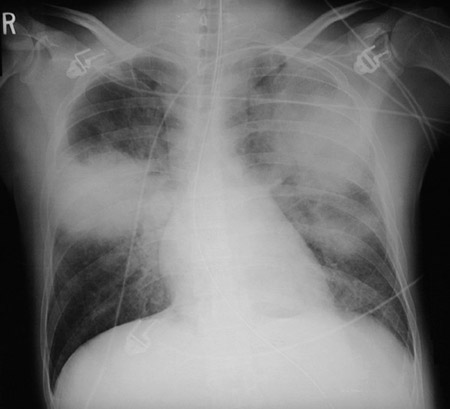

| This PA chest radiograph demonstrates extensive bilateral infiltrates made even more dense through hemorrhage from vascular damage by infection with Pseudomonas aeruginosa. The film below was taken only two hours after the one above, indicating how virulent this process can be. |